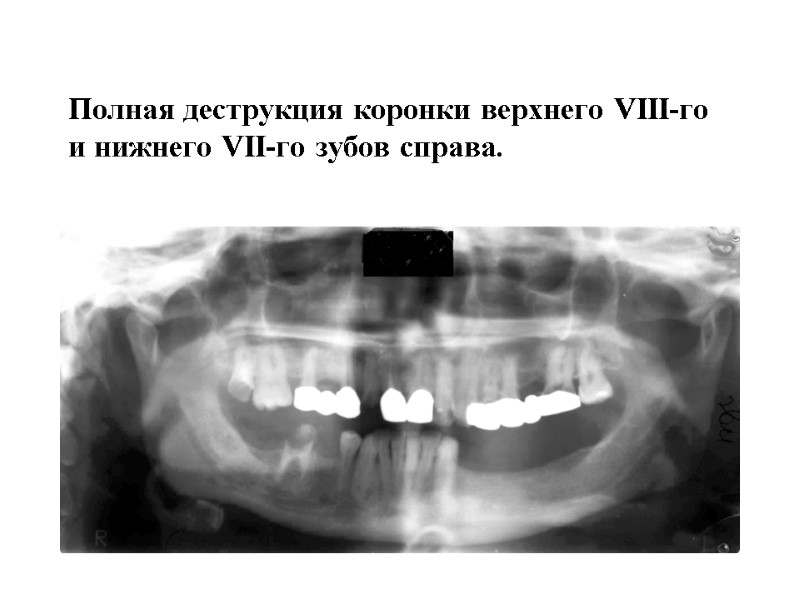

Полная деструкция коронки верхнего VIII-го и нижнего VII-го зубов справа.